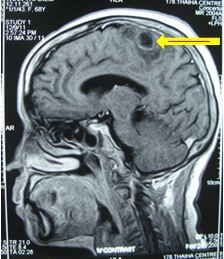

Chụp MRI sọ não (12/12/2011):

Hình 2: Hình ảnh chụp MRI sọ não có khối u não vùng đỉnh trái, 20×19mm, ngấm thuốc quanh u

Chụp MRI sọ não: Sau xạ phẫu 6 tháng bằng dao gamma quay: khối u não tan biến hoàn toàn

Trước điều trị: u não 20×19mm

Sau điều trị 6 tháng: u tan hoàn toàn

Hình 6: Hình ảnh chụp MRI sọ não sau 6 tháng xạ phẫu bằng dao gamma quay: Khối u não di căn vùng đỉnh trái tan hoàn toàn